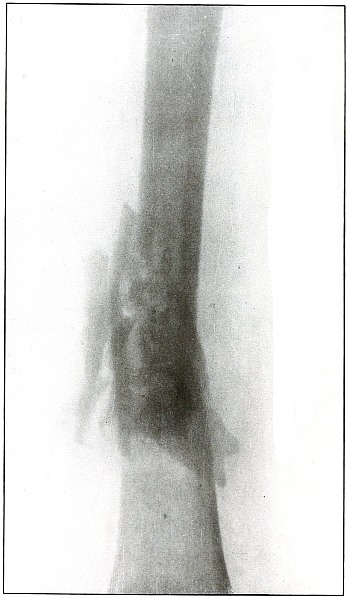

Plate 54.

[Pg 119]

Rifle—Plate 54.

LOWER EXTREMITY.

Gunshot Fracture of the Lower End of the Shaft of the Femur.

The course of the bullet was anteroposterior through the axis of the

femur. Several large fragments which were not displaced were separated

by the force of impact. The separation of the fragments and the

overriding of the ends of the proximal and distal large fragments were

due to bearing bodily weight or to muscular contraction.

The projectile causing the wound was moving with the velocity of mid

range. The wound of exit was not lacerated.

The emergency treatment is antiseptic dressing and temporary splint

immobilization. Permanent dressing, with extension and lateral

compression, is the rule.

Infection in such cases is frequent owing to lack of facilities for

proper dressing on the field.

Results in saving life and limb are generally good.

[Pg 120]